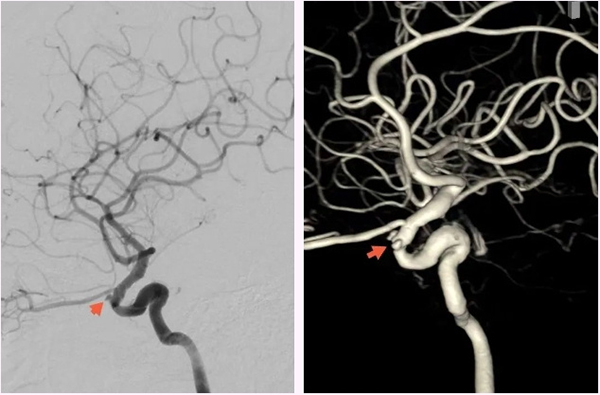

▲脑血管造影显示右侧颈内动脉海绵窦段假性动脉瘤

次日,神经外科脑血管病介入团队行DSA检查发现:1.右侧颈内动脉海绵窦段前膝处两个小假性动脉瘤,对应管腔狭窄;2.颈内动脉海绵窦瘘,流量小;3.右侧脑膜中动脉前支供血的脑膜动静脉瘘。鼻出血的“元凶”找到了,就是颈内动脉海绵窦段假性动脉瘤。脑血管病介入团队于全麻下为患者实施了颈动脉覆膜支架置入术,术中采用了“特洛伊木马”技术,利用中间导管将Willis覆膜支架(4.0*10)输送至病变处,精准定位,球囊充盈后,支架贴壁良好,术后即刻造影,假性动脉瘤消失。